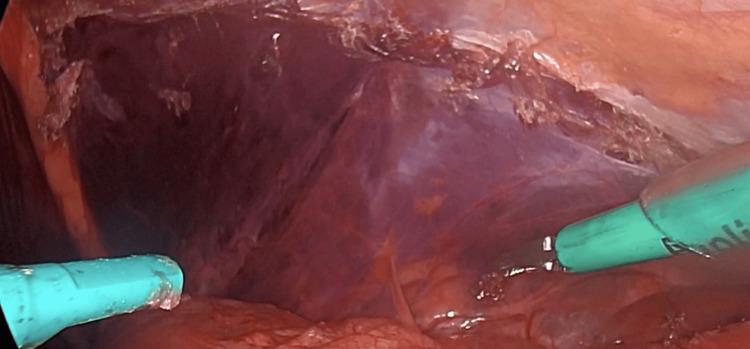

Inguinal hernia repair is one of the most common surgical procedures. Traditionally, traumatic fixations have been used to prevent mesh migration, resulting in chronic pain in the groin. However, a non-traumatic alternative with cyanoacrylate glue is offered. A 50-year-old male patient underwent elective surgery for inguinal hernia repair. During the surgery, it was decided to use cyanoacrylate glue for mesh fixation without complications. In his follow-up consultation, the patient showed a satisfactory course. The use of cyanoacrylate glue, a synthetic resorbable adhesive, for more rapid wound closure has shown favorable results. It is characterized by a low rate of complications and a significant decrease in groin pain in the short- and medium-term. This technique is considered a viable and effective alternative for the reduction of complications, with promising clinical results.